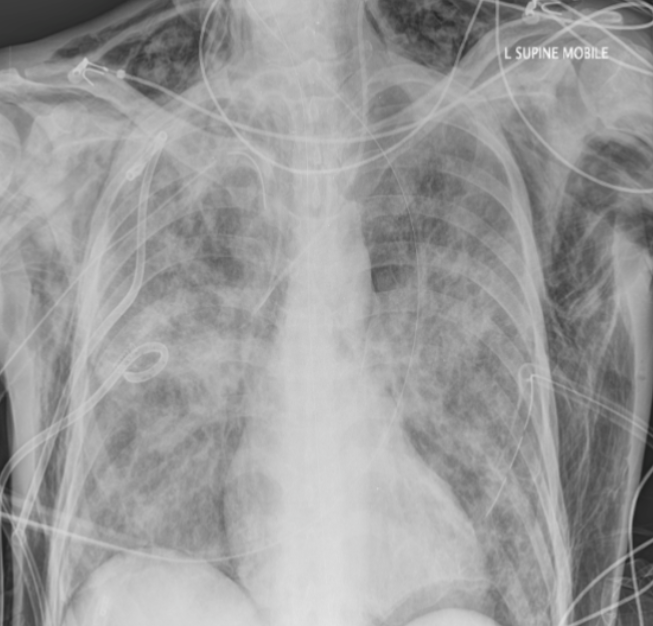

what is happening in this patient?

Severe subcutaneous emphysema (gas leaking into muscle tissues)